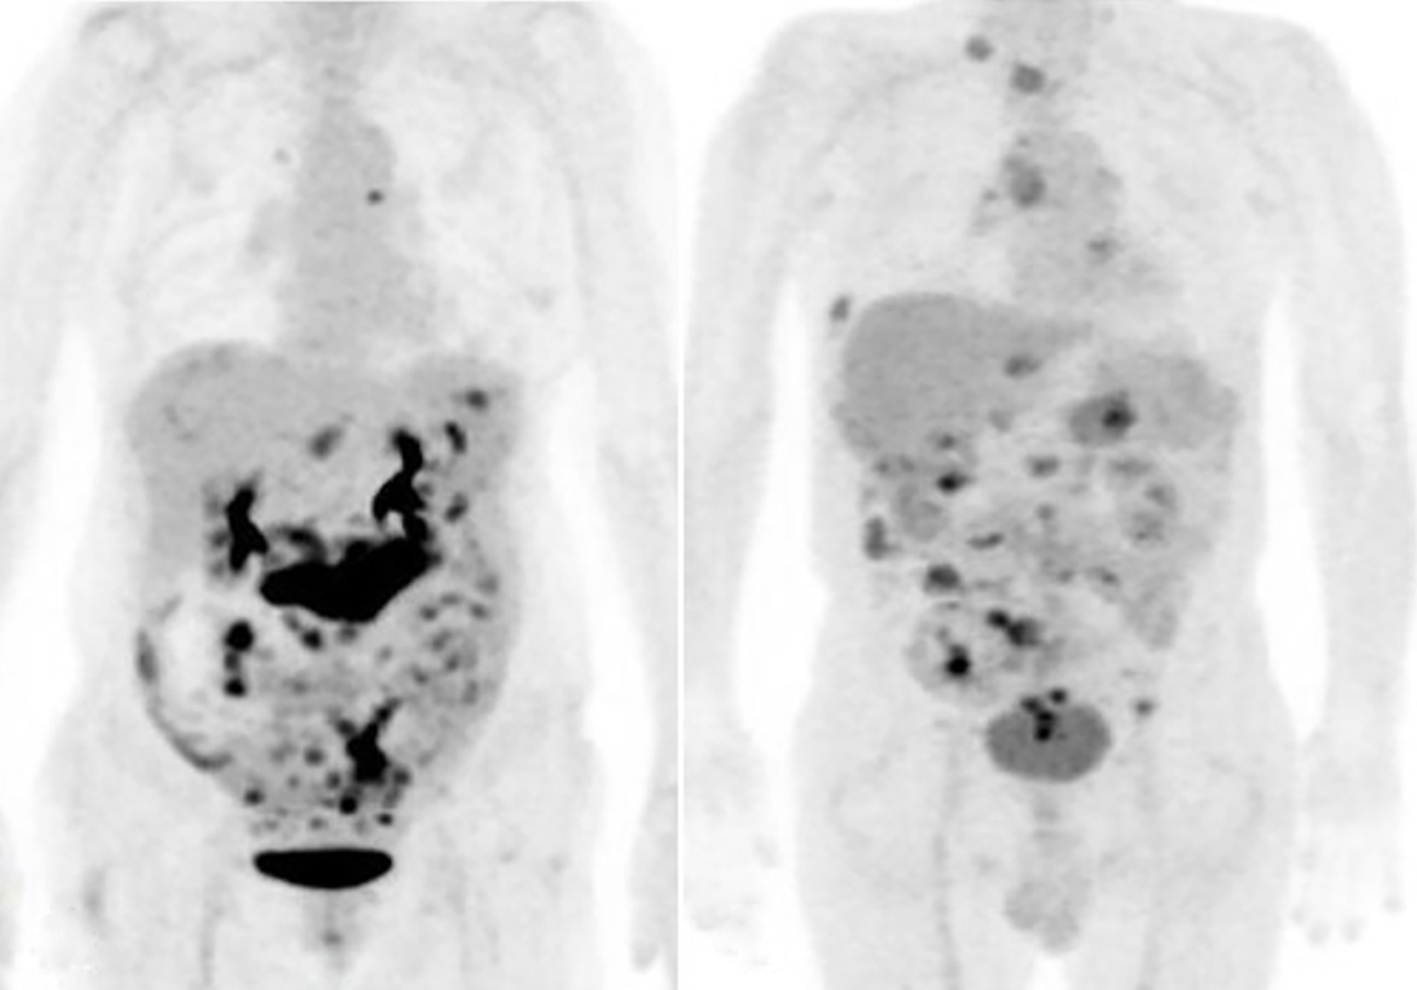

Importantly, preoperative imaging plays a crucial role in understanding disease extent and informing

surgical strategies. Future studies should compare the outcomes of advanced imaging modalities, such as MRI or PET scans, with conventional CT to provide a more comprehensive evaluation of disease burden and anatomical complexities (16-19). The relatively high PCI scores observed in our study suggest that, despite the challenges, palliative surgery can facilitate the maintenance of dietary intake throughout overall survival, enhancing quality of life during patients' remaining lifespan (fig. 1).

Figure 1 - PET scans shows high PCI scores (a) Case 7 with 27 PCI score; (b) Case 10 with 23 PCI score